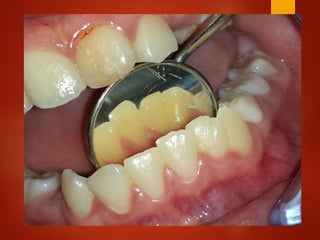

El documento es un registro médico odontológico que muestra las fechas de las visitas de un paciente al centro de salud El Raval, incluyendo exámenes y tratamientos realizados como la extracción de cálculos salivales en abril y mayo de 2012.